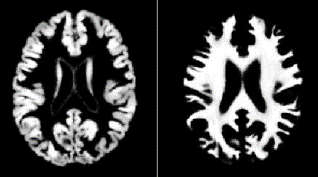

【図2】大脳皮質VBM解析例

左側は灰白質、右側は白質を示している。